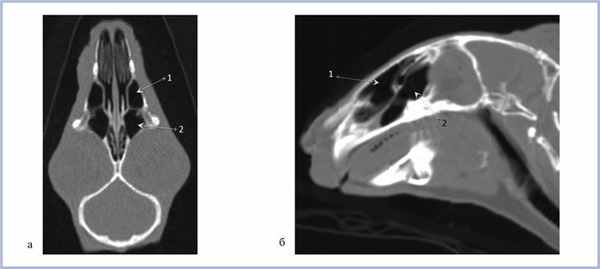

Верхнечелюстная пазуха у кролика делится на 3 широко сообщающиеся между собой полости, располагающиеся одна над другой [2]. С полостью носа верхнечелюстная пазуха сообщается через соустье, расположенное впереди решетчатой кости (рис. 1) [17].

Рис. 1. Полость носа и верхнечелюстные пазухи взрослого кролика.

На рис. 2 представлены верхнечелюстные пазухи кролика в возрасте 3 нед в различных проекциях; на рис. 3 в возрасте 6 мес. Таким образом, у кроликов уже в возрасте 3 нед определяются сформированные верхнечелюстные пазухи.

Рис. 2. Компьютерная томография околоносовых пазух кролика в возрасте 3 нед.